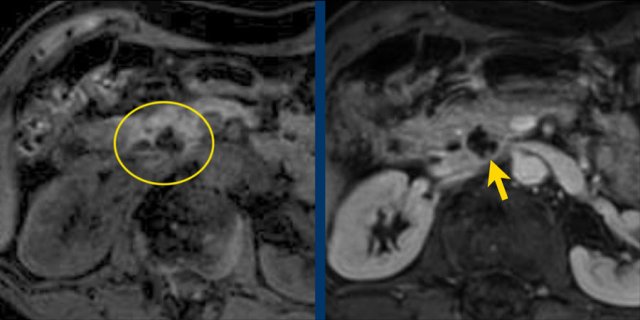

Another branch-duct IPMN found on screening with two nodules (circle and arrow).

T1W-images with fatsat before (left image) and after contrast (right image).

EUS with contrast agent revealed 2 foci without enhancement most likely mucus plugs.

6 years later the cyst was unchanged.

75 year old male with a 2.7 cm side branch IPMN in the pancreatic head (circle).

During follow up one year later dilatation of pancreatic duct was seen.

EUS showed a resectable adenocarcinoma.